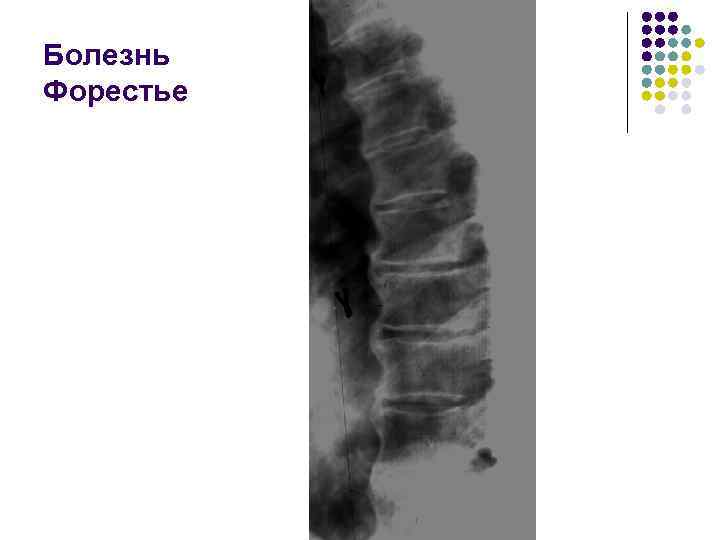

Болезнь Форестье (фиксирующий гиперостоз) 1. Чаще поражается грудной отдел с дальнейшим распространением на шейный и поясничный 2. Происходит костеобразование под передней продольной связкой толщиной до 1 -1, 5 см 3. Тела позвонков утолщены из-за периостальных наслоений 4. Высота межпозвоночных дисков не изменена 5. Дугоотросчатые крестцово-подвздошные, реберно-позвоночные суставы не страдают. На начальном этапе спондилёз и болезнь Форестье не различимы

Болезнь Форестье

l На рентгенограмме грудного отдела позвоночного столба в боковой проекции определяются признаки выраженных, распространенных дистрофических изменений в виде болезни Форестье за счет характерных костных разрастаний под передней продольной связкой практически во всех визуализированных отделах грудной части позвоночника. На этом фоне отмечаются также явления умеренного и также распространенного отсеохондроза – сужение межпозвонковых простанств, субхондральный остеосклероз, соответствующие костные разрастания. Положение тел позвонков правильное, деструктивных изменений нет.